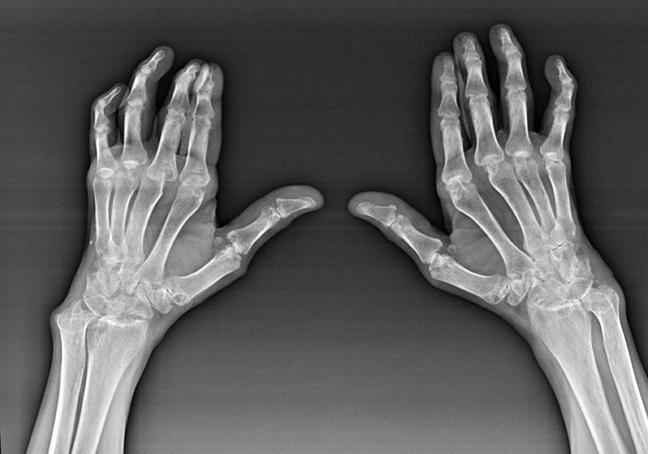

Rheumatoid arthritis

Rheumatoid arthritis is a disease in which the human immune system damages body tissues.In other words, rheumatoid arthritis is an autoimmune pathology.This disease is also systemic, since many tissues are affected (Muscles, joints, glasses, etc.) and organs (Heart, kidneys, lungs, etc.) in the body.

Despite the fact that rheumatoid arthritis is a systemic disease under it, to a greater extent, the joints suffer, while the injury of other tissues and organs is in the background.With this disease, almost all types of shrubs can be affected (P bracest worlds, carpal routes, metacarpio-phallange, interphalanxic joints).The injury is usually symmetrical (those.The same joints are affected) In both hands, accompanied by swelling, pain in damaged joints.In the morning, during the lifting of the bed, there is some rigidity in the affected joints, which can last approximately 1 hour and then disappear without a trace.

Very often with rheumatic arthritis near the affected joints of the brush (More often piano-piange joints, interphalánxis) Rheumatoid nodules appear.They are a rounded formation located under the skin.In the brush, these formations arise more frequently on the back.On palpation, they are dense, inactive, painless.The number of them can vary.